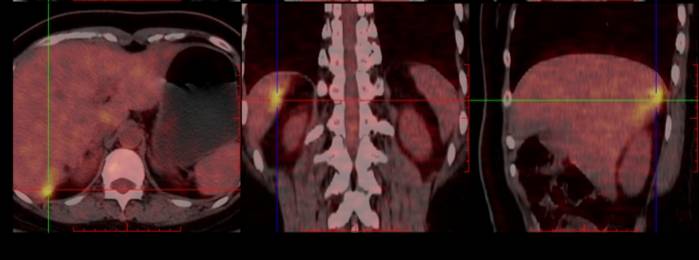

PET-CT: 1、①卵巢癌术后,子宫及双附件缺如,阴道残端未见明确肿瘤征象。②肝S7段包膜下稍低密度灶,FDG代谢增高,考虑转移。③左侧髂外血管旁肿大淋巴结,FDG代谢增高,转移可能大。④左侧盆底(乙状结肠左旁)结节伴高代谢,倾向转移灶。2、双侧筛窦及左侧上颌窦炎。双侧扁桃体区对称性FDG代谢增高,考虑炎性增生。3、右肺上叶前段结节,FDG代谢未见明显异常增高,倾向炎性病变。双肺多发小增殖灶。4、肝内多发囊肿。 5、双侧肾上腺结节,考虑腺瘤。6、腹膜后、双侧腹股沟多发增大淋巴结,炎性增生可能性大。

PET-CT(2022年11月1日):对比2022年1月6日PET-CT,1、①卵巢癌术后改变,阴道残端未见明确肿瘤征象,较前相仿;②盆底腹膜、左下腹膜局部明显增厚伴FDG代谢增高,FDG代谢增高,较前新发,考虑转移;③肝脏术后改变考虑,局部少量积液;④右侧心膈角肿大淋巴结伴FDG代谢增高,较前新发,考虑转移;⑤肠系膜间隙、结肠旁及腹膜后多发淋巴结,部分FDG代谢略增高,较前相仿。2、左侧筛窦及左侧上颌窦炎。双侧扁桃体炎。3、右肺上叶前段结节,FDG代谢未见明显异常增高,较前相仿,倾向炎性病变。4、肝内多发囊肿,较前相仿。肝右叶钙化灶。5、右侧肾上腺显示欠清,左侧肾上腺略增生,较前大致相仿。6、双侧腹股沟多发炎性增生淋巴结,较前相仿。